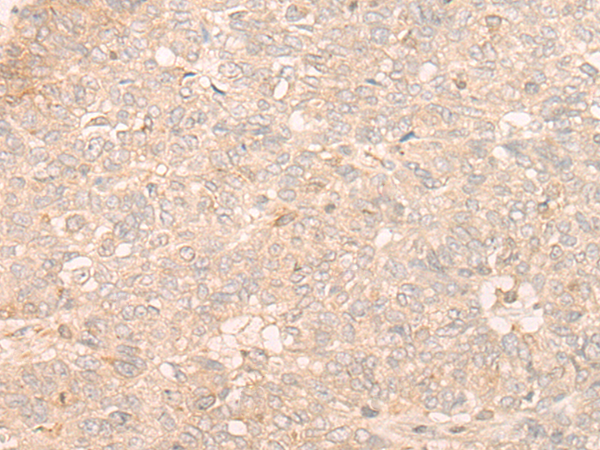

分类: 科研抗体货号: P06372别名: DMT; EPB49应用: WB,IHC反应种属: Human, Mouse